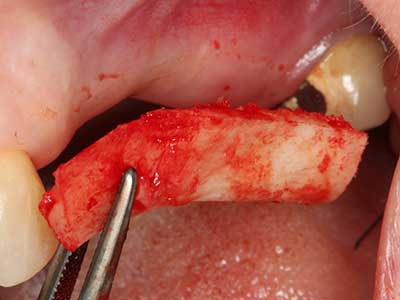

En la extracción de bloques óseos la piezocirugía también presenta ventajas adicionales: Además de la alta precisión en la osteotomía que ya se ha descrito antes, se ha comprobado que el uso de los delgados insertos de sierra resulta especialmente cuidadosas con el hueso. Frente a esto, sobre todo cuando se usan las fresas de Lindemann, cabe esperar pérdidas en la extracción significativamente más altas debido al mayor grosor de la parte frontal del cabezal (Lakshmiganthan, Gokulanathan et al. 2012). La separación basal que se necesita en particular en los injertos de bloque extraídos de forma retromolar se ve facilitada mediante sierras perpendiculares especialmente previstas a tal fin, lo que permite considerar que la cirugía piezoeléctrica es un procedimiento preciso y seguro para la obtención de bloques de hueso en el área retromolar (Happe 2007) (fig. 1-12).